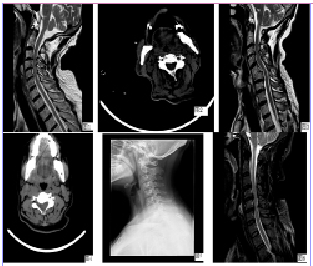

颈椎病ct图片讲解

颈椎病ct图片讲解,颈椎ct图片图解

颈椎病的ct诊断